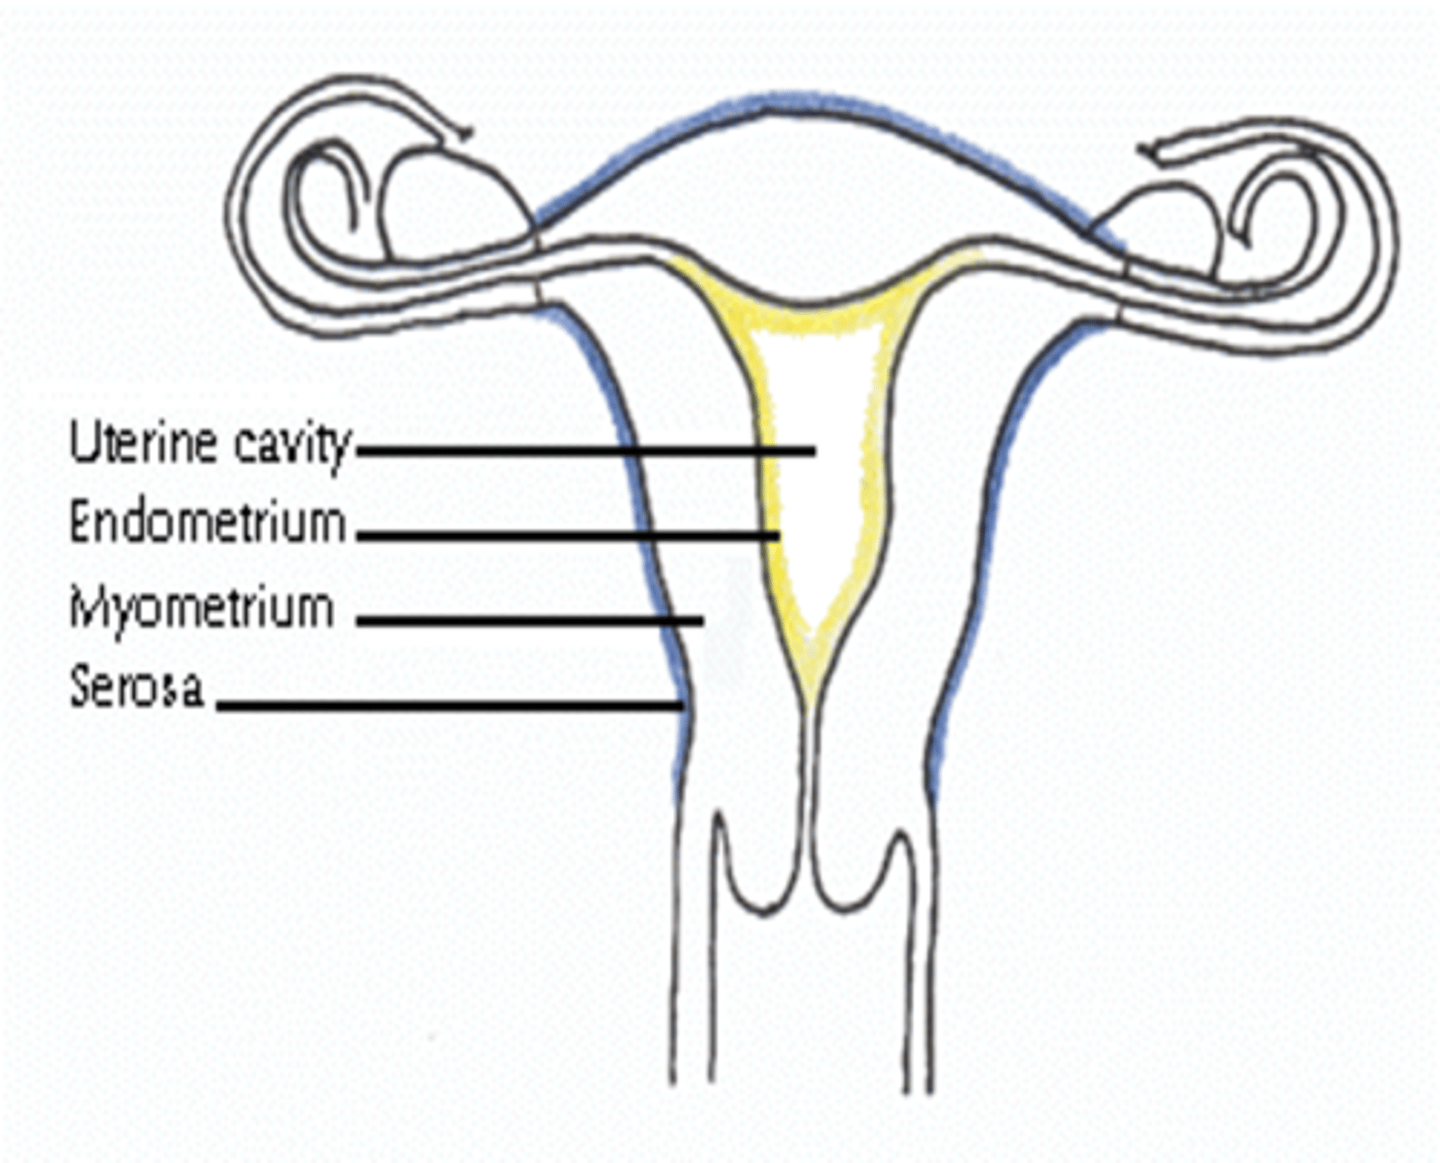

What are the 3 layers of the uterine walls?

inner- endometrium

middle- myometrium

outer- serosa

What is serosa also called?

perimetrium

The endometrial cavity is continuous with the ___

vaginal canal

What is the widest and most superior part of the uterus?

fundus

What is the largest part of the uterus?

corpus / body

What is the uterine isthmus also called?

lower uterine segment